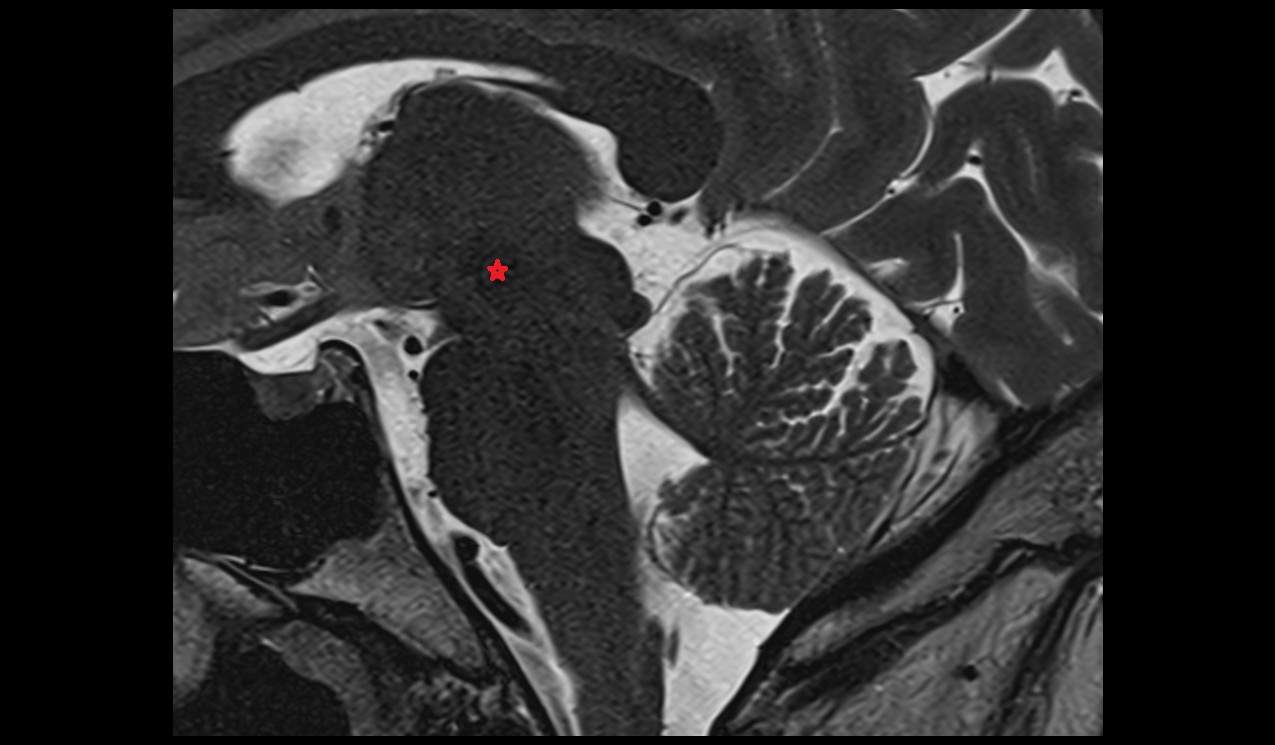

- Peripheral zone of prostate

- Anterior Fibromuscular Stroma of prostate

- Central zone of prostate

- Transitional zone of prostate